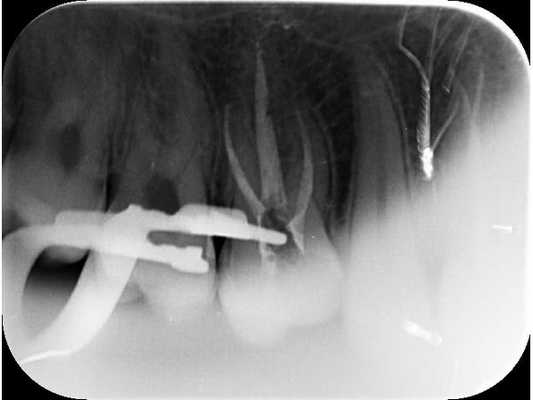

Клиническое наблюдение за больными осуществляли непосредственно после лечения, а также спустя 2 года. До лечения и в отдаленные сроки пациентам проводилась рентгенография.

Через 2 года после лечения было обследовано 33 пациента. 32 из них жалоб не предъявляли. При клиническом осмотре слизистая оболочка десны в проекции верхушек корней была без видимых патологических изменений, пломбы сохранены, перкуссия безболезненная. У одного пациента периодически возникали боли от горячего в излеченном зубе, а вертикальная перкуссия была слабо болезненной. Зуб перелечен витальной экстирпацией. При рентгенологическом обследовании 5 пациентов с первоначальными незначительными изменениями в периодонте у 2 пациентов выявлены эти изменения. Они остались не увеличенными. В 3 случаях изменения в периапикальных тканях имели тенденцию к замещению склерозированной костной тканью. Таким образом, во всех 33 случаях наблюдалось клиническое благополучие, в 31 случае - рентгенологическое. Положительные результаты лечения через два года получены в 94% случаев.